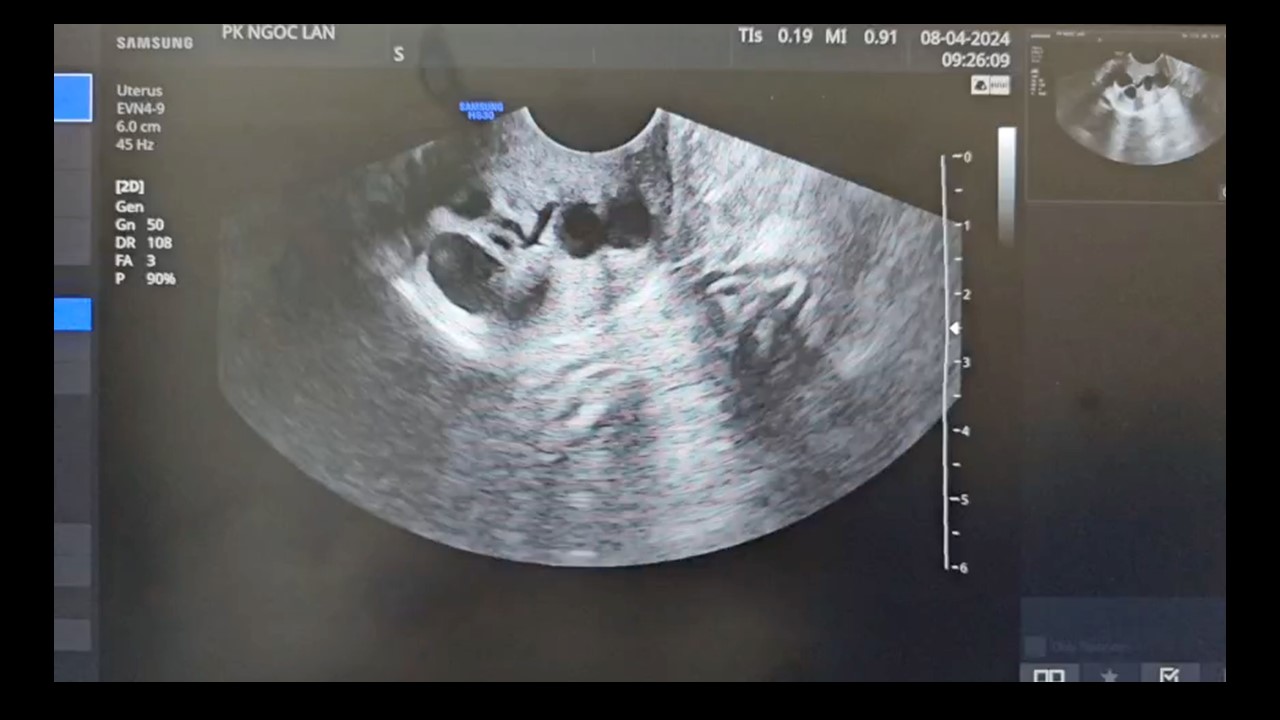

Vai trò của siêu âm trong chẩn đoán và điều trị hiếm muộn